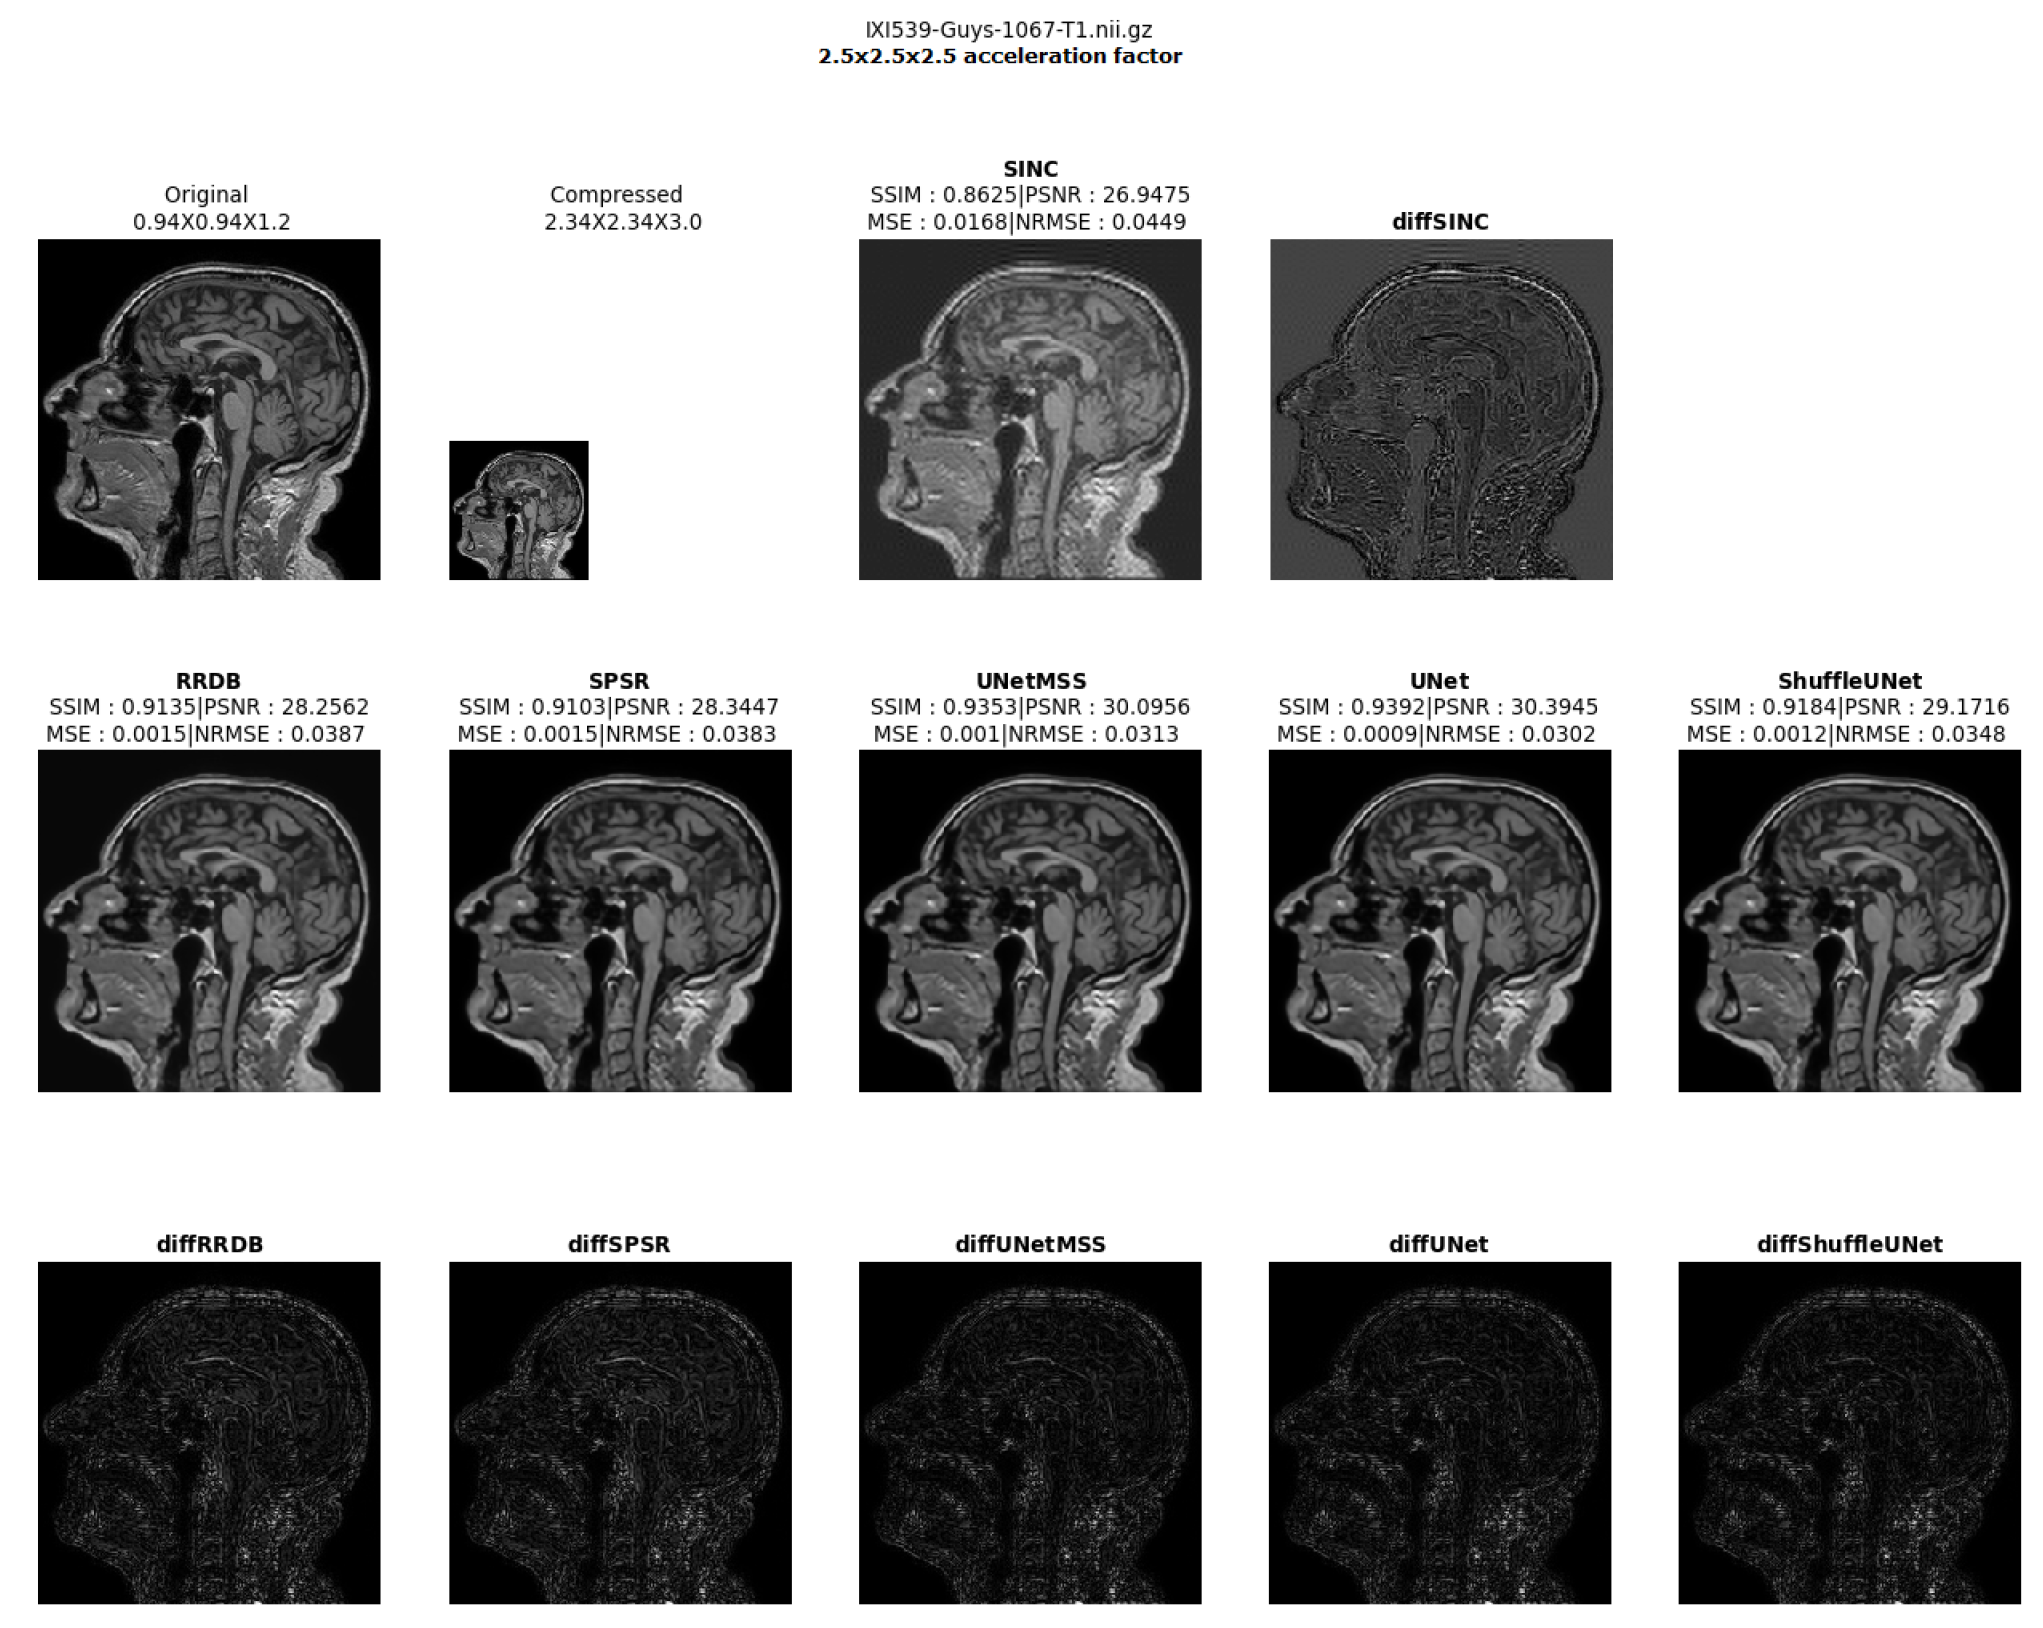

- Visualising individual model results for all the acceleration factors.

Different 3D CNN Models Results Comparison for Cross Acceleration Factor of IXI-T1 Dataset